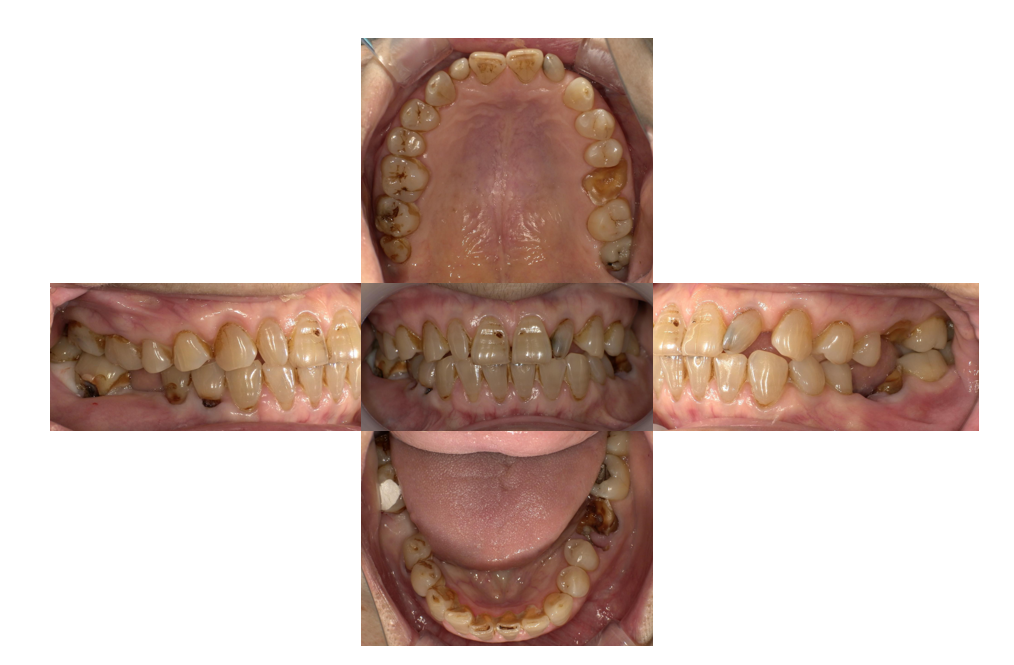

症例3

治療後

| 主訴 | 歯を入れたい |

「右下」67欠損 |

| 治療内容 | 右下67左下6インプラント、左上⑤6⑦ジルコニアブリッジ |

| 年齢・性別 |

68歳 男性 |

| 治療期間 |

8ヶ月 |

| 治療費用 | ①左上⑤6⑦ジルコニアブリッジ¥264000 ②右下67左下6インプラント(3本) 診査診断¥22000+一次手術(京セラ)¥825000+左下6GBR¥110000+上部構造¥429000 総額¥1386000 |

| リスク・副作用 | インプラント周囲炎、インプラント上部構造の緩み |